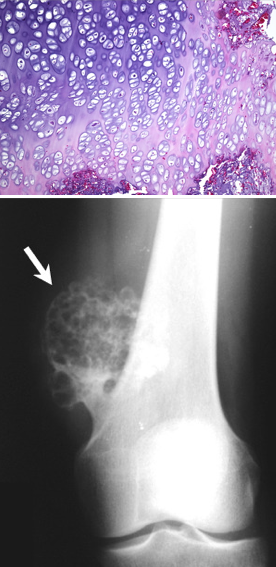

A 23 year old male presents with an enlarging mass on the side of his knee over the past few months. The biopsy and radiograph are shown below. What is your diagnosis? Prognosis?

Benign osteochondroma. These tumore originate from long metaphysis and are encased by a cartilaginous cap as seen in his biopsy.